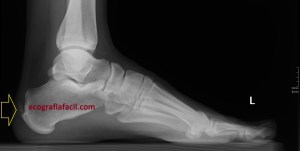

Corrobora si el paciente tiene estudios radiológicos simples que estén en concordancia con la imagen 10, por ejemplo, la imagen 12.

La flecha amarilla indica la que en la parte posterior del calcáneo existe un calcio tosco en esta rx lateral del pie en carga, pero es en la inserción, cuidado con esto, cuando se produce el Haglund, no es en la inserción, es antes, y se debe a la exostosis mencionada con anterioridad, mira, compara imagen 12 e imagen 13. La flecha roja es indicativa de Síndrome de Haglund.

13